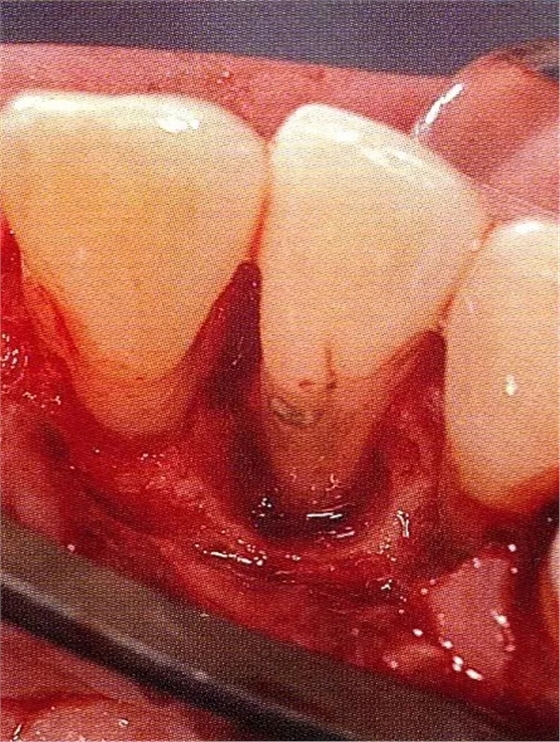

▲圖7-4術(shù)后1年2個月再翻開看的情況。與圖7-1的骨缺損狀態(tài)相比可知形成了臨床性骨再生。

▲圖7-5此狀態(tài)下,左下5的遠中存在牙槽骨不平整,因此進行了骨修整。同時,將骨膜留存,進行了齦瓣根尖側(cè)移動術(shù),去除了牙周袋。